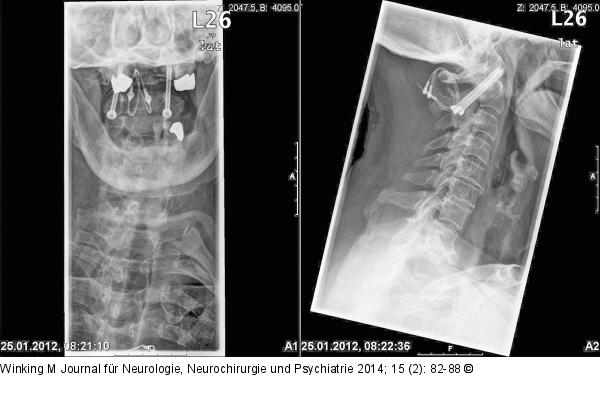

Abbildung 6: Rheumatische Wirbelsäule Röntgenaufnahmen nach transartikulärer Verschraubung von HWK 1 und 2 mit zusätzlicher Beckenkammspaninterposition, die mit einer Titan-Kabelcerclage gesichert wurde. |

Röntgenaufnahmen nach transartikulärer Verschraubung von HWK 1 und 2 mit zusätzlicher Beckenkammspaninterposition, die mit einer Titan-Kabelcerclage gesichert wurde. |